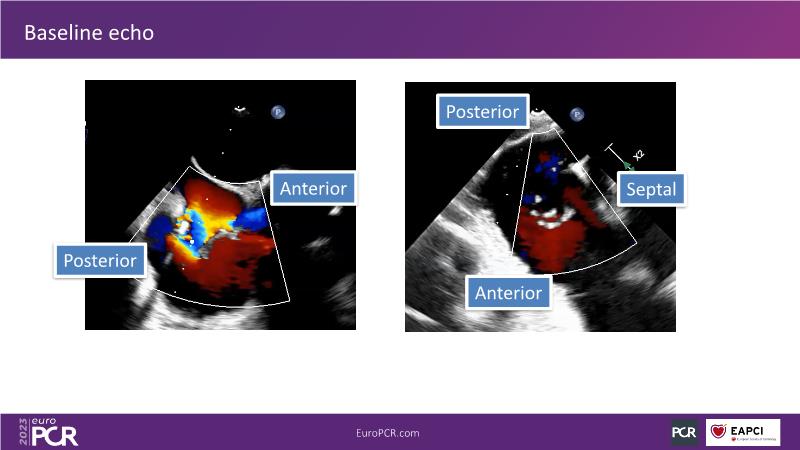

Tailoring tricuspid regurgitation patient treatment with the PASCAL Precision system

Watch this session to discuss exciting cases of tricuspid regurgitation, learn about the proposed new integrated classification for tricuspid regurgitation and enjoy a live presentation of the PASCAL Precision Repair System using a beating heart simulator, among others!

- To discuss the different tricuspid regurgitation phenotypes that can be treated with the PASCAL Precision repair system

- To participate in a case-based discussion using the PASCAL Precision repair system for the treatment of tricuspid regurgitation